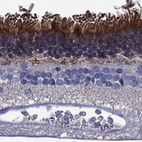

Immunohistochemical staining of human retina shows strong cytoplasmic positivity in photoreceptor cells.